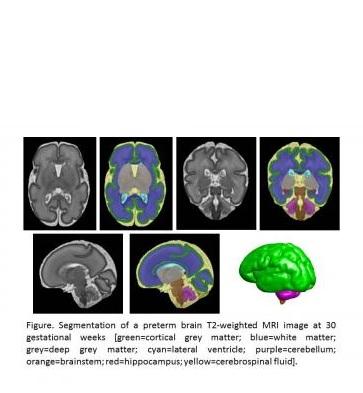

- l'apport lipidique est positivement associé aux volumes cérébelleux et du tronc cérébral chez les nouveau-nés prématurés de très faible poids de naissance (Voir visuel ci-contre IRM cérébrale d’un bébé prématuré à 30 semaines de grossesse. Le vert représente la matière grise corticale, le bleu la substance blanche, le gris la matière grise profonde, le violet le cervelet, le rouge l’hippocampe).